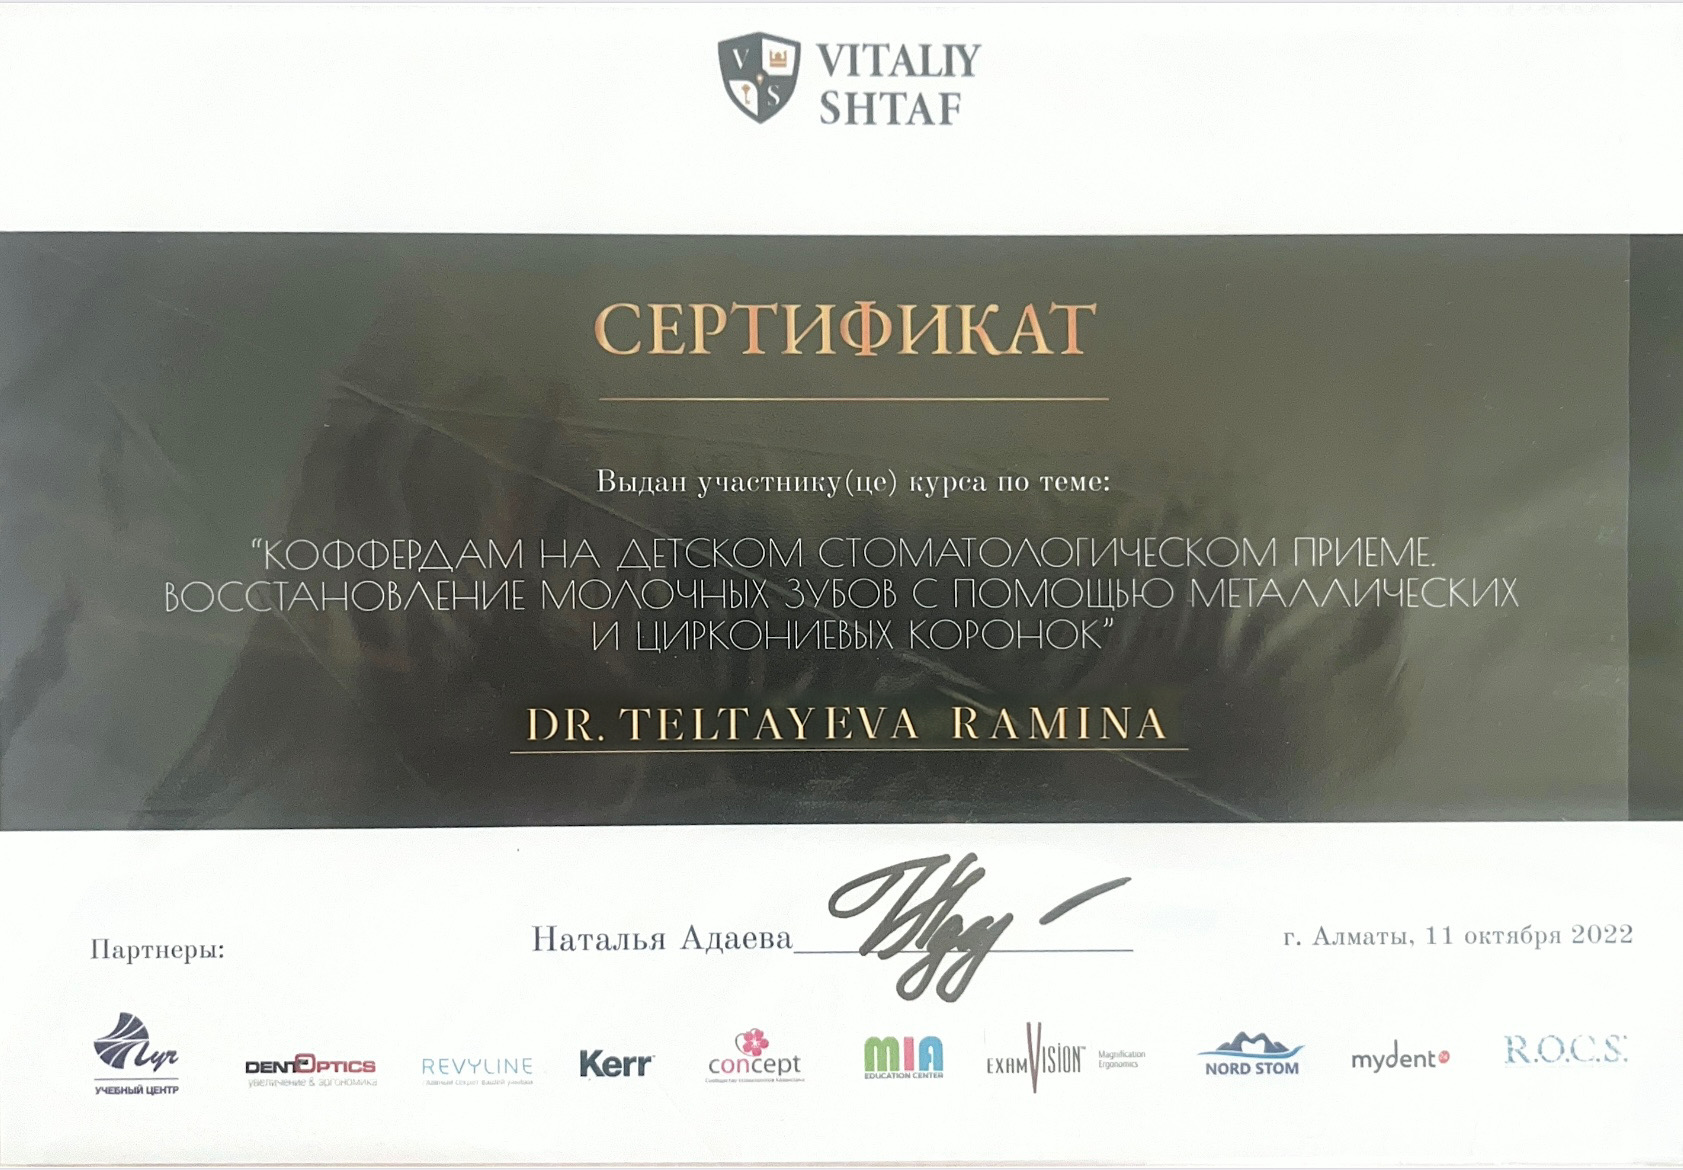

Прошла обучение у врачей из Кореи, Японии, Беларуси и России